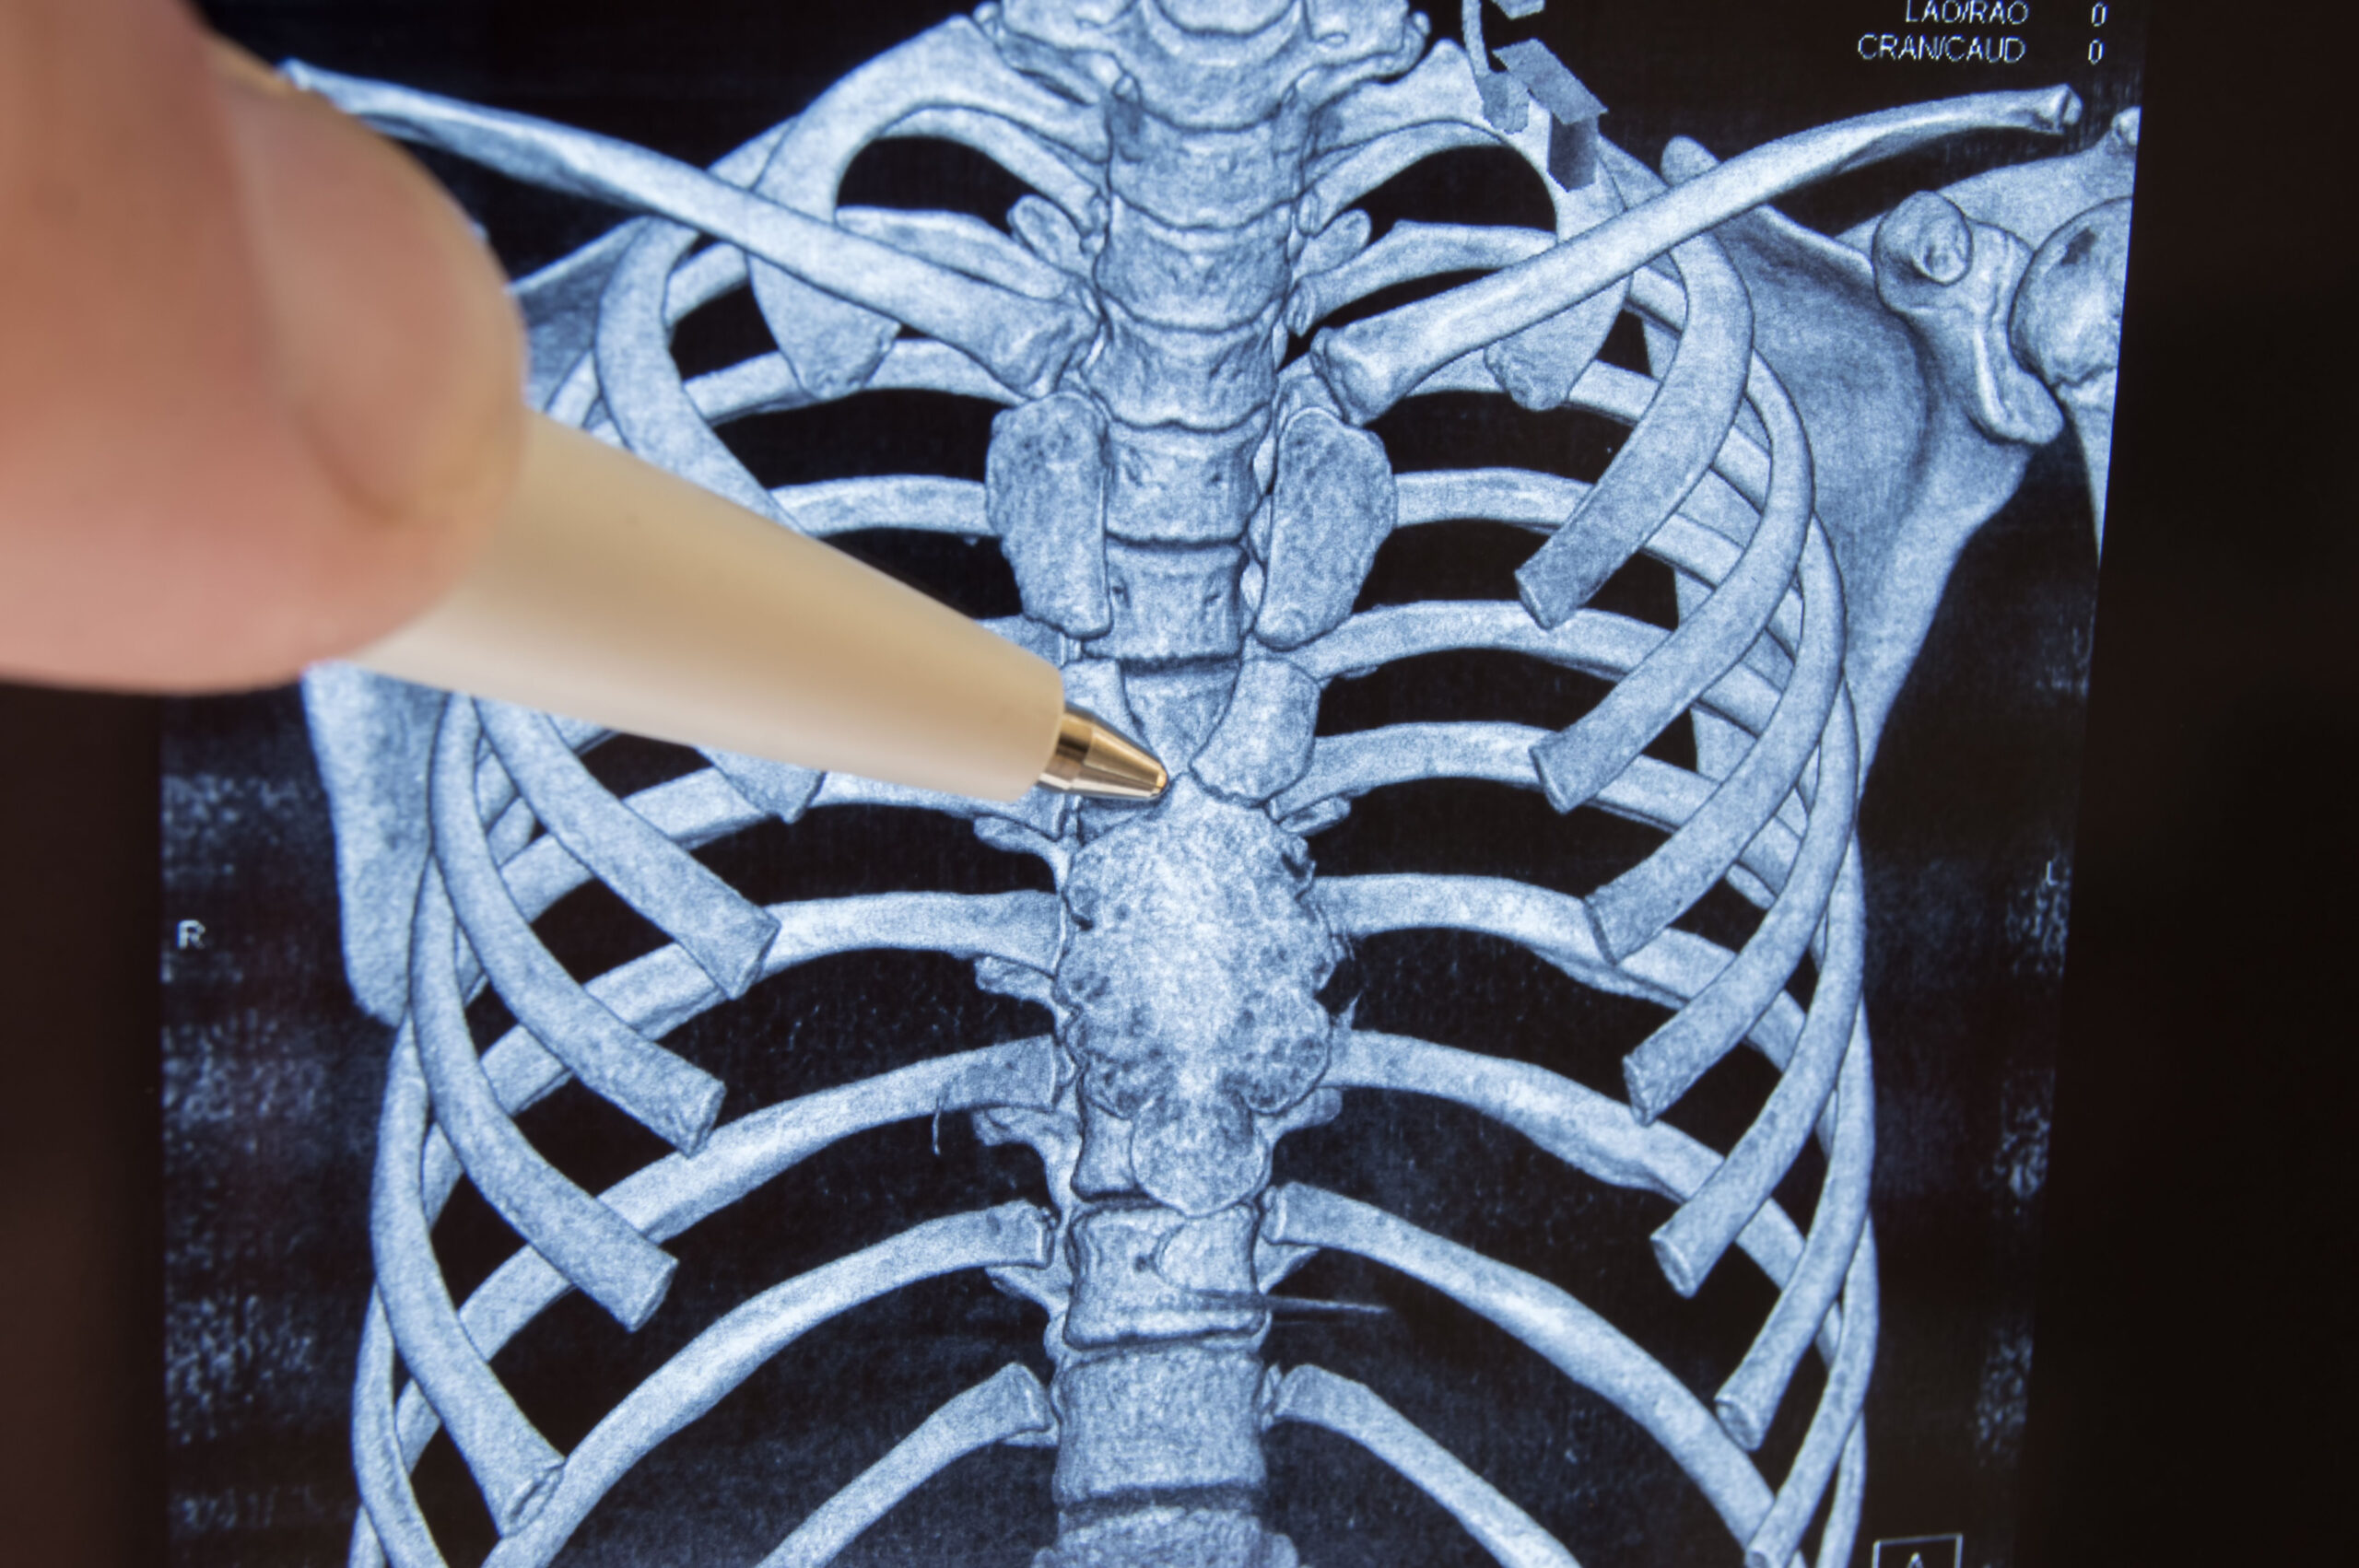

ПЕРЕЛОМ 10 РЕБРА слева и РАК ЛЕГКИХ на КТ расшифровке (второе мнение)

Компьютерная томография (КТ) грудной полости

Мультиспиральная КТ в диагностике тупой торакальной и абдоминальной травмы